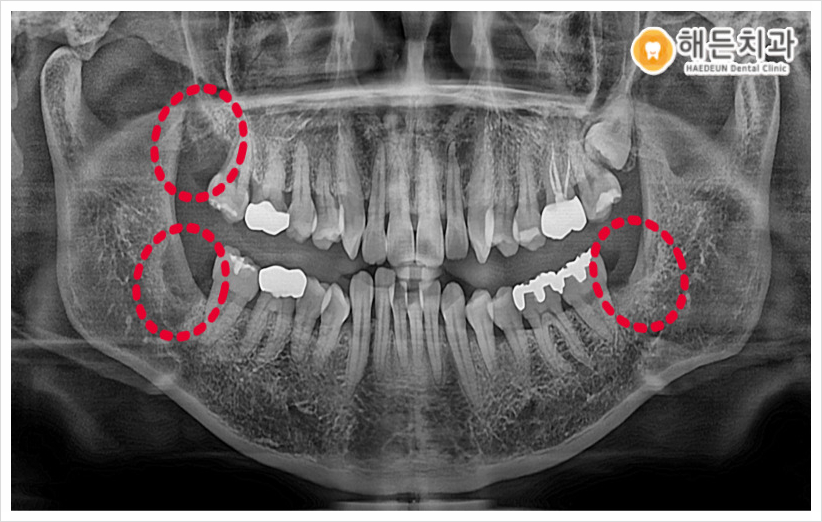

오늘 소개해 드릴 분께서는

사랑니를 4개 다 가지고 계셨는데요.

왼쪽 위 사랑니를 제외하고는

치아머리가 잇몸 밖으로 일부 나와있어

앞에 큰 어금니와 사이에 음식물이 많이 껴

잇몸이 자주 붓고 아프셨고

특히 오른쪽 위 사랑니는 양치도 힘들어

관리도 잘 안된다며 발치를 원하셨습니다. (ㅠㅠ)

아직 왼쪽 위 사랑니는 잇몸 위로 맹출 되지 않아아

환.자분께서 불편함이 없는 상태라

추후 뽑으시기로 하셨습니다.